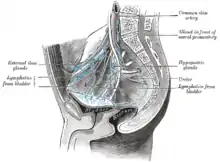

The most common sites for bladder cancer metastases are the lymph nodes, bones, lung, liver, and peritoneum.[78] The most common sentinel lymph nodes draining bladder cancer are obturator and internal iliac lymph nodes. The location of lymphatic spread depends on the location of the tumors. Tumors on the superolateral bladder wall spread to external iliac lymph nodes. Tumors on the neck, anterior wall and fundus spread commonly to the internal iliac lymph nodes.[79] From the regional lymph nodes (i.e. obturator, internal and external lymph nodes) the cancer spreads to distant sites like the common iliac lymph nodes and paraaortic lymph nodes.[80] Skipped lymph node lesions are not seen in bladder cancer.[79]

A bilateral pelvic lymphadenectomy should accompany radical cystectomy. At minimum, a standard template of lymphadenectomy should be followed by removing the external and internal iliac and obturator lymph node.[124] When performing a lymphadenectomy, the surgeon can either remove lymph nodes from a smaller (standard) or from larger (extended) area. In comparison with a standard lymph node dissection, having an extended dissection may reduce a person's likelihood of death from any reason, including dying from bladder cancer.[125] The extended procedure may lead to more serious unwanted effects and may or may not influence the likelihood of the cancer recurring over time.[125] The rate of not-so-serious side effects may be similar for both surgeries.[125]